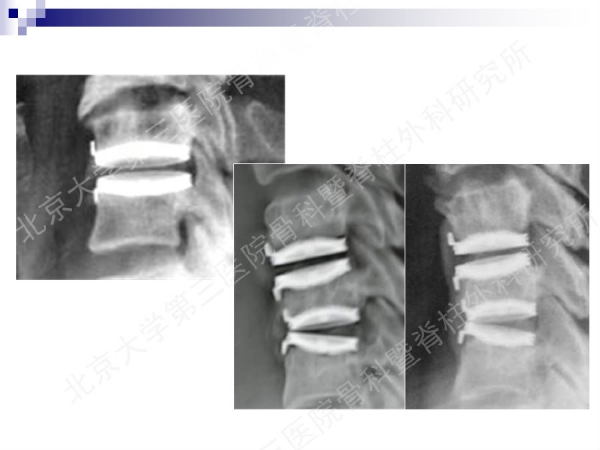

今天,在北京大学第三医院骨科暨脊柱外科研究所刘忠军教授分享的《颈椎人工椎间盘置换手术注意问题》课件中,他将通过大量影像资料、临床研究数据和长期随访结果,给大家介绍现阶段最重要的颈椎非融合技术——人工椎间盘置换术的适应证、禁忌证和其他需要密切注意的一些问题,提醒同道关注与手术技术及内植物相关的尺寸、终板顺列、中心轴线顺列等问题,严格把控手术指征,规范、精准地开展颈椎人工椎间盘置换手术,保障手术疗效。